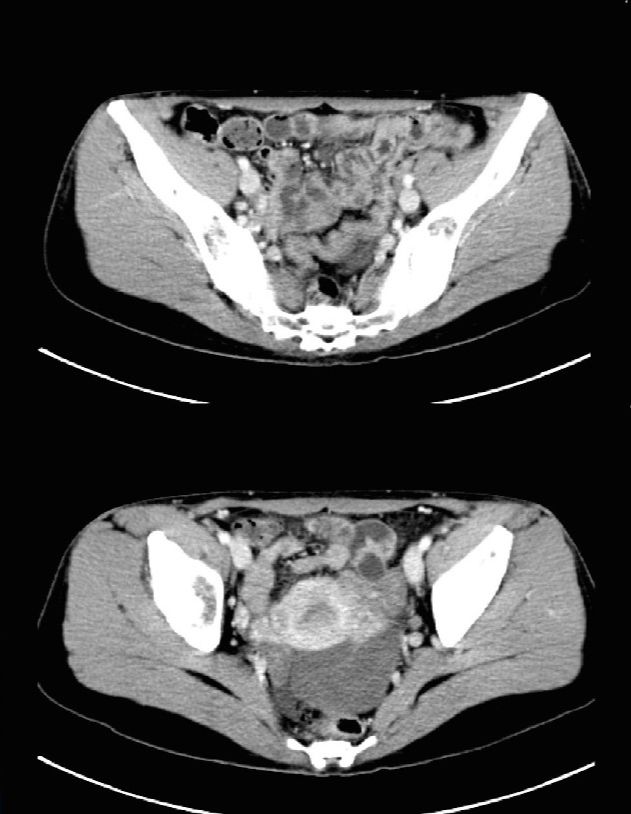

2018-2-2复查CT疗效评估进展。

2018-2-2~2018-7-19行二线9周期紫杉醇+赫赛汀方案化疗:紫杉醇120mg(90mg/m2) d1、8,赫赛汀264mg d1(6mg/kg)。

疗效评估:肿瘤标志物下降,影像评估SD。

二线治疗

2018-8-9~2019-3-7行二线9周期紫杉醇方案化疗:紫杉醇180mg(120mg/m2) d1、赫赛汀264mg d1(6mg/kg)。